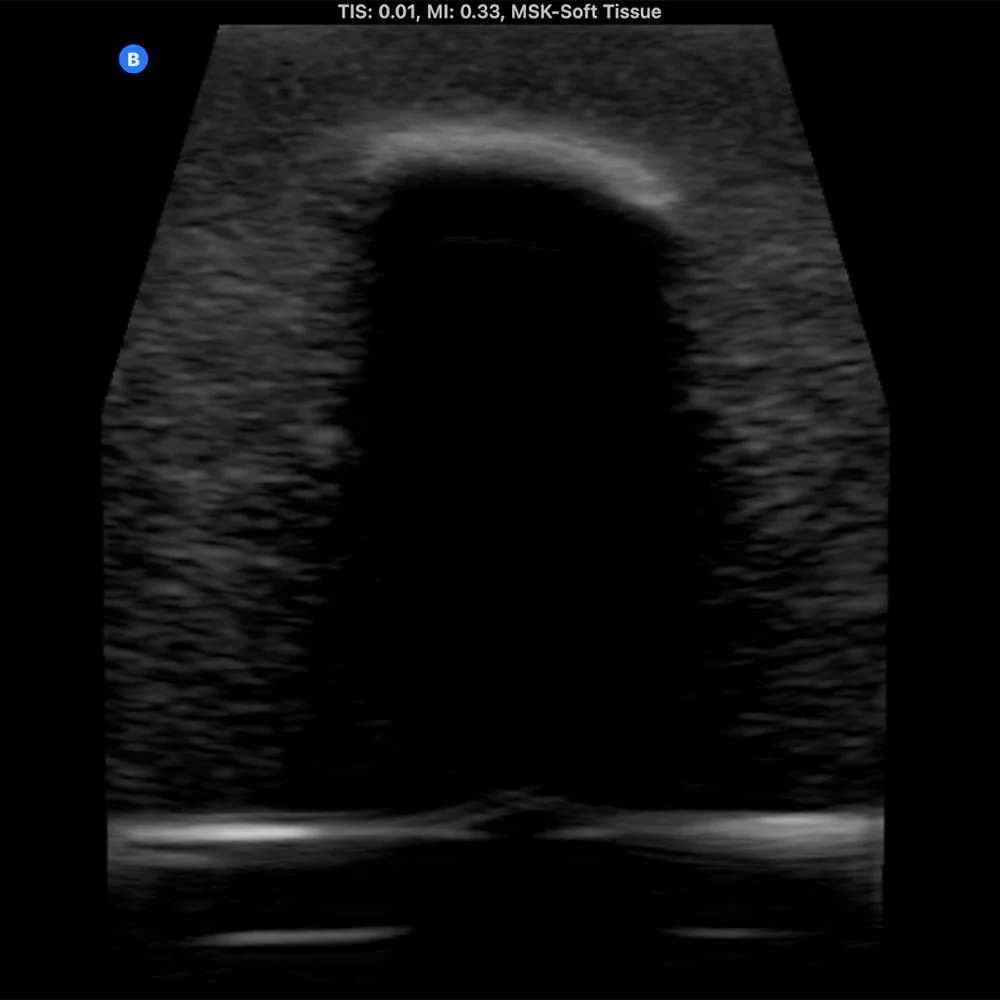

The Bone Fracture Ultrasound Phantom is an excellent training aid for developing the skills needed to identify bone fractures within soft tissue.

- Five bones incorporated within the model (three positioned superficially and two at a deeper level).

- One healthy bone with no fracture, plus four bones featuring fractures of varying severity.

- Produces outstanding ultrasound image quality.